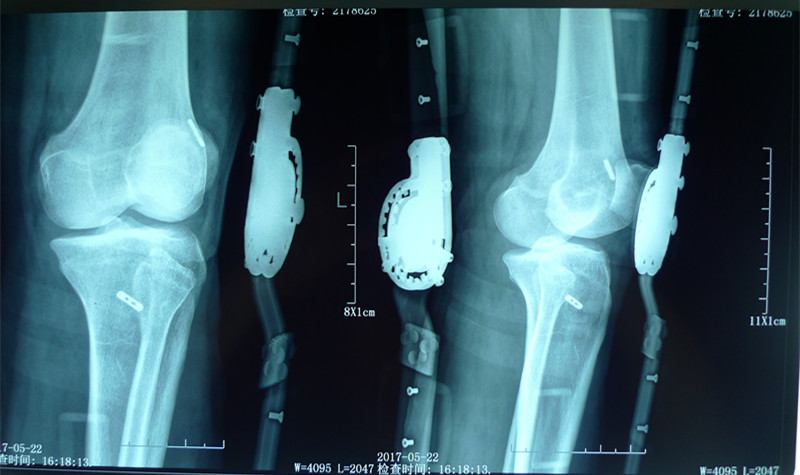

图为患者术后核磁

膝关节交叉韧带的全内重建技术,尽可能的少取移植物,尽可能短的骨隧道,使得手术更加微创,尤其是多发韧带损伤时优势明显,本2例患者术中仅取一条半腱肌,即完成前交叉韧带重建,达到治疗目的同时又能尽可能多的保留自体组织,最大化降低对自身组织的损伤,患者术后可以尽快恢复运动水平。同时锁扣带袢钛板的应用允许移植物在各种程度牵张后达到有效固定,定位器的应用,可以更加准确的定位股骨端的内外口,可以让术者更加容易观察及操作股骨隧道的建立,通过全内技术,尽可能的保留股骨及胫骨骨量。其中手术的关键在于:1、精准测量骨道和修整移植物长度;2、理顺股骨与胫骨隧道的引线,防止移植物在关节内缠绕。